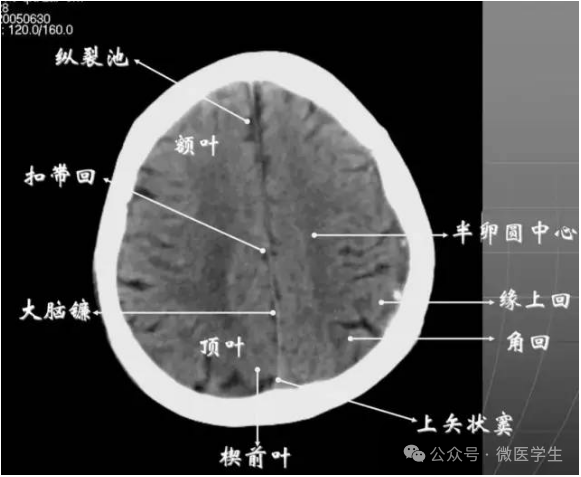

内侧壁侧脑室体部被胼胝体分开,侧脑室体部的外方为顶叶,顶枕沟及中央沟将大脑为为额、顶、枕叶。

在胼胝体和侧脑室上方,大脑镰自前向后贯穿中线。白质部分为半卵圆中心,额叶范围缩小,顶叶所占比例扩大,枕叶基本消失。

- 半卵圆中心:位于胼胝体上方,由左右大脑半球髓质形成的有髓纤维,对称位于大脑镰两侧区域。

已近颅顶,大脑镰清晰可见,其旁的脑灰质和脑沟十分清楚。顶叶较小,额叶较小。

- 放射冠:是内囊到大脑皮质间的放射状纤维白质。